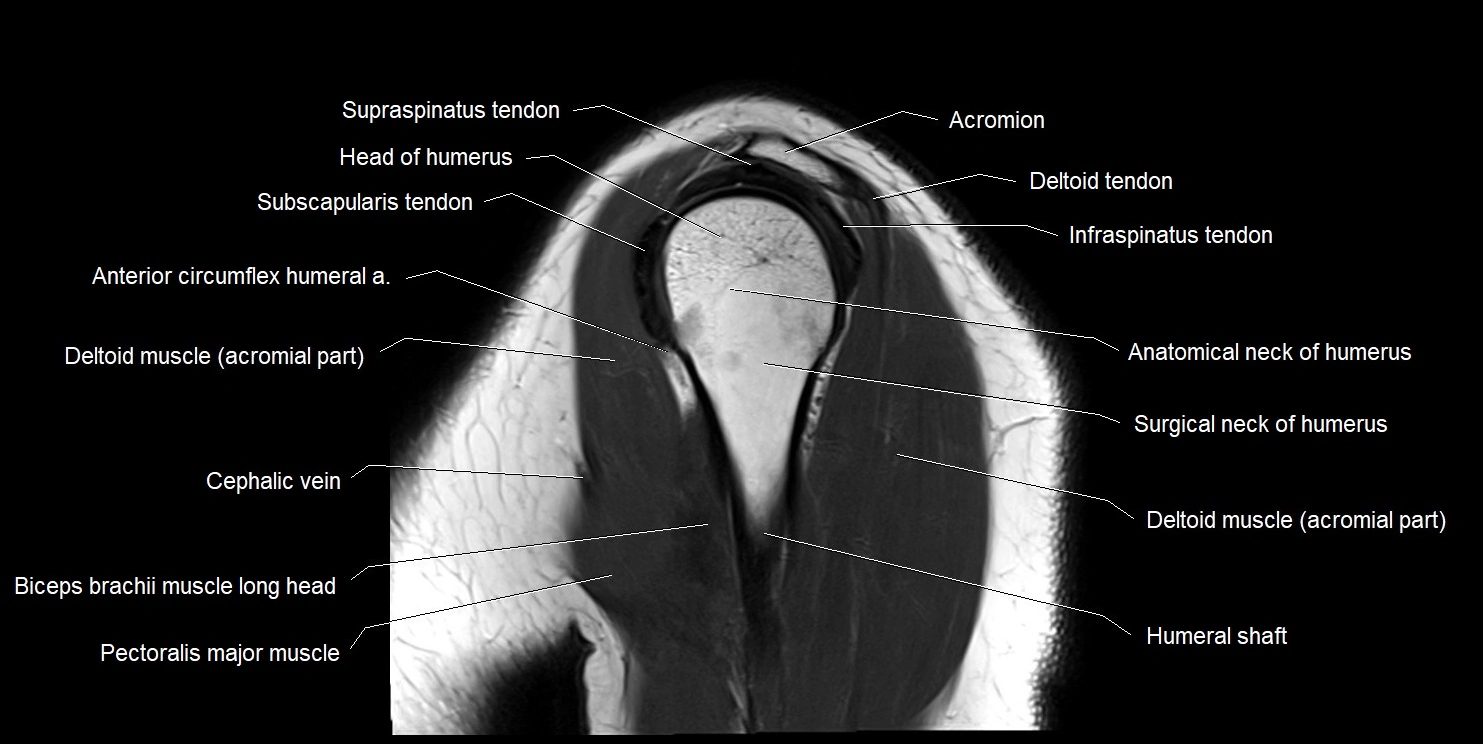

MRI images

image